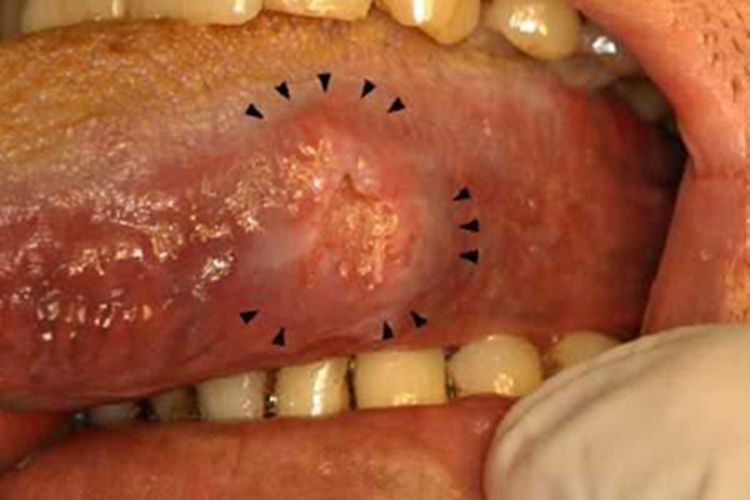

舌癌舌头边缘可有一较大糜烂面,周围组织颜色加深、肿胀,中央血运较差,为黄白色质硬凹陷,缺损明显,边缘皮肤不平整。可感到疼痛明显。